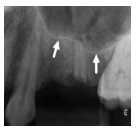

Marque a alternativa que apresenta o reparo anatômico destacado na imagem abaixo (setas):